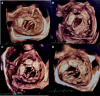

Case summary: In this case report, we present the percutaneous closure of PVL of mitral valve replacement (MVR), in a patient with cardiogenic shock who failed conservative medical treatment and was deemed inoperable due to recurrent operations. Successful closure of the PVL with the use of the four consecutive PVL closure devices was performed under general anaesthesia with guidance of 2D and 3D transoesophageal echocardiography. The procedure was performed with no complications and the patient has remained asymptomatic after 10 months following the PVL closure procedure with marked improvement in her NYHA class and echocardiographic values.